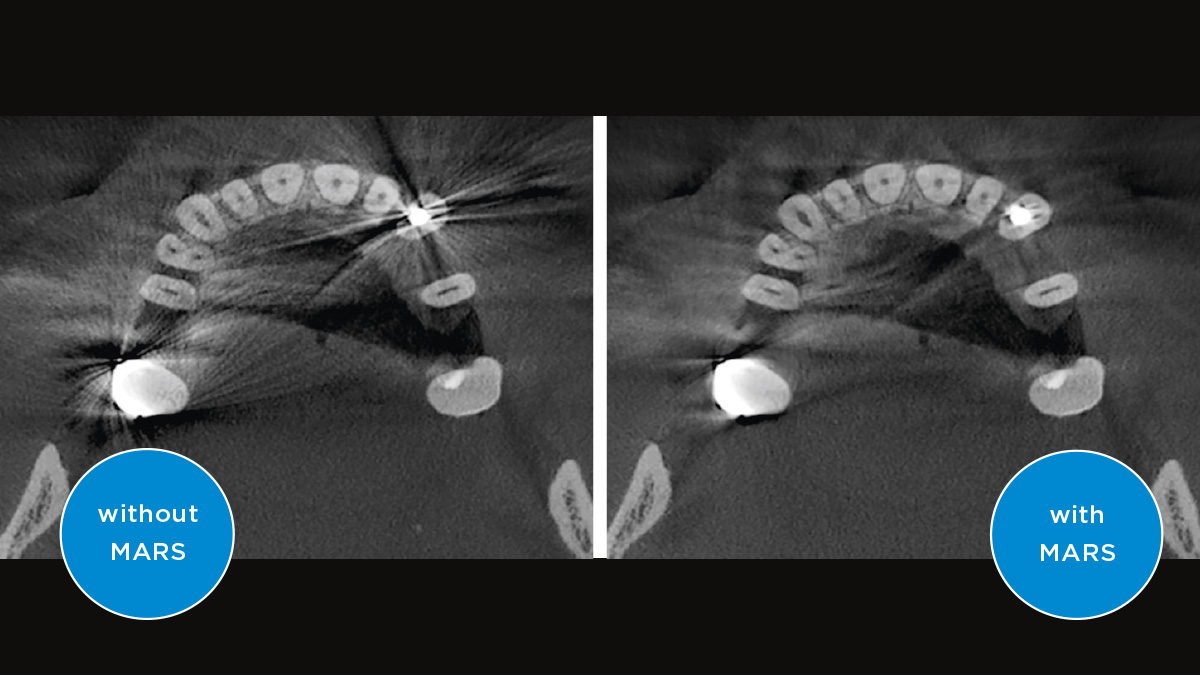

Der Direct Conversion Sensor (DCS) hat den Standard der Panorama-Bildgebung neu definiert. Röntgenstrahlen werden direkt in elektrische Signale umgewandelt – im Gegensatz zu herkömmlichen Systemen gibt es keinen Signalverlust durch Lichtumwandlung, was eine verbesserte Bildgebung ermöglicht. Das Ergebnis sind Bilder mit einer sehr hohen Schärfe, selbst bei niedriger Dosis.